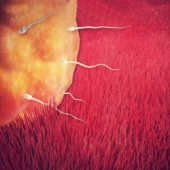

This is time when the common pregnancy signs are very likely to appear while your baby has just become an embryo and is hiding safely in placenta. You might not feel any different yet, but the amniotic cavity, which will be filled with fluid, and the placenta, which will bring oxygen and nutrients to nourish your baby, are forming in your uterus.

Your Baby:

- Called embryo.

- An important period when organs and nervous system are forming.

- Development of placenta allowing blood to flow at the end of the week.